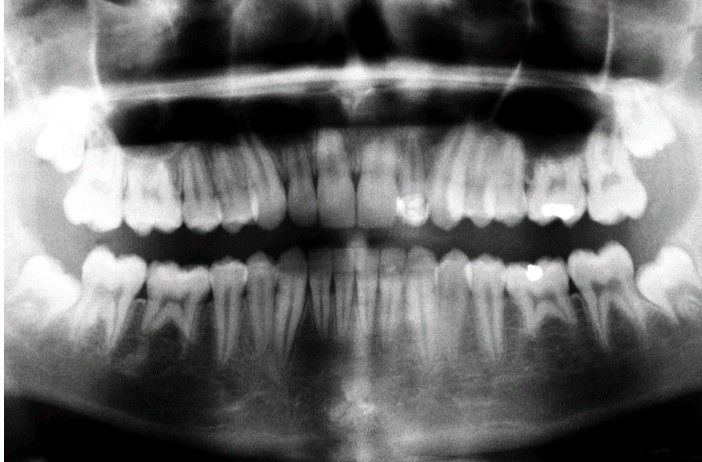

External resorption

First molars in all four quadrants demonstrate extensive radicular external resorption